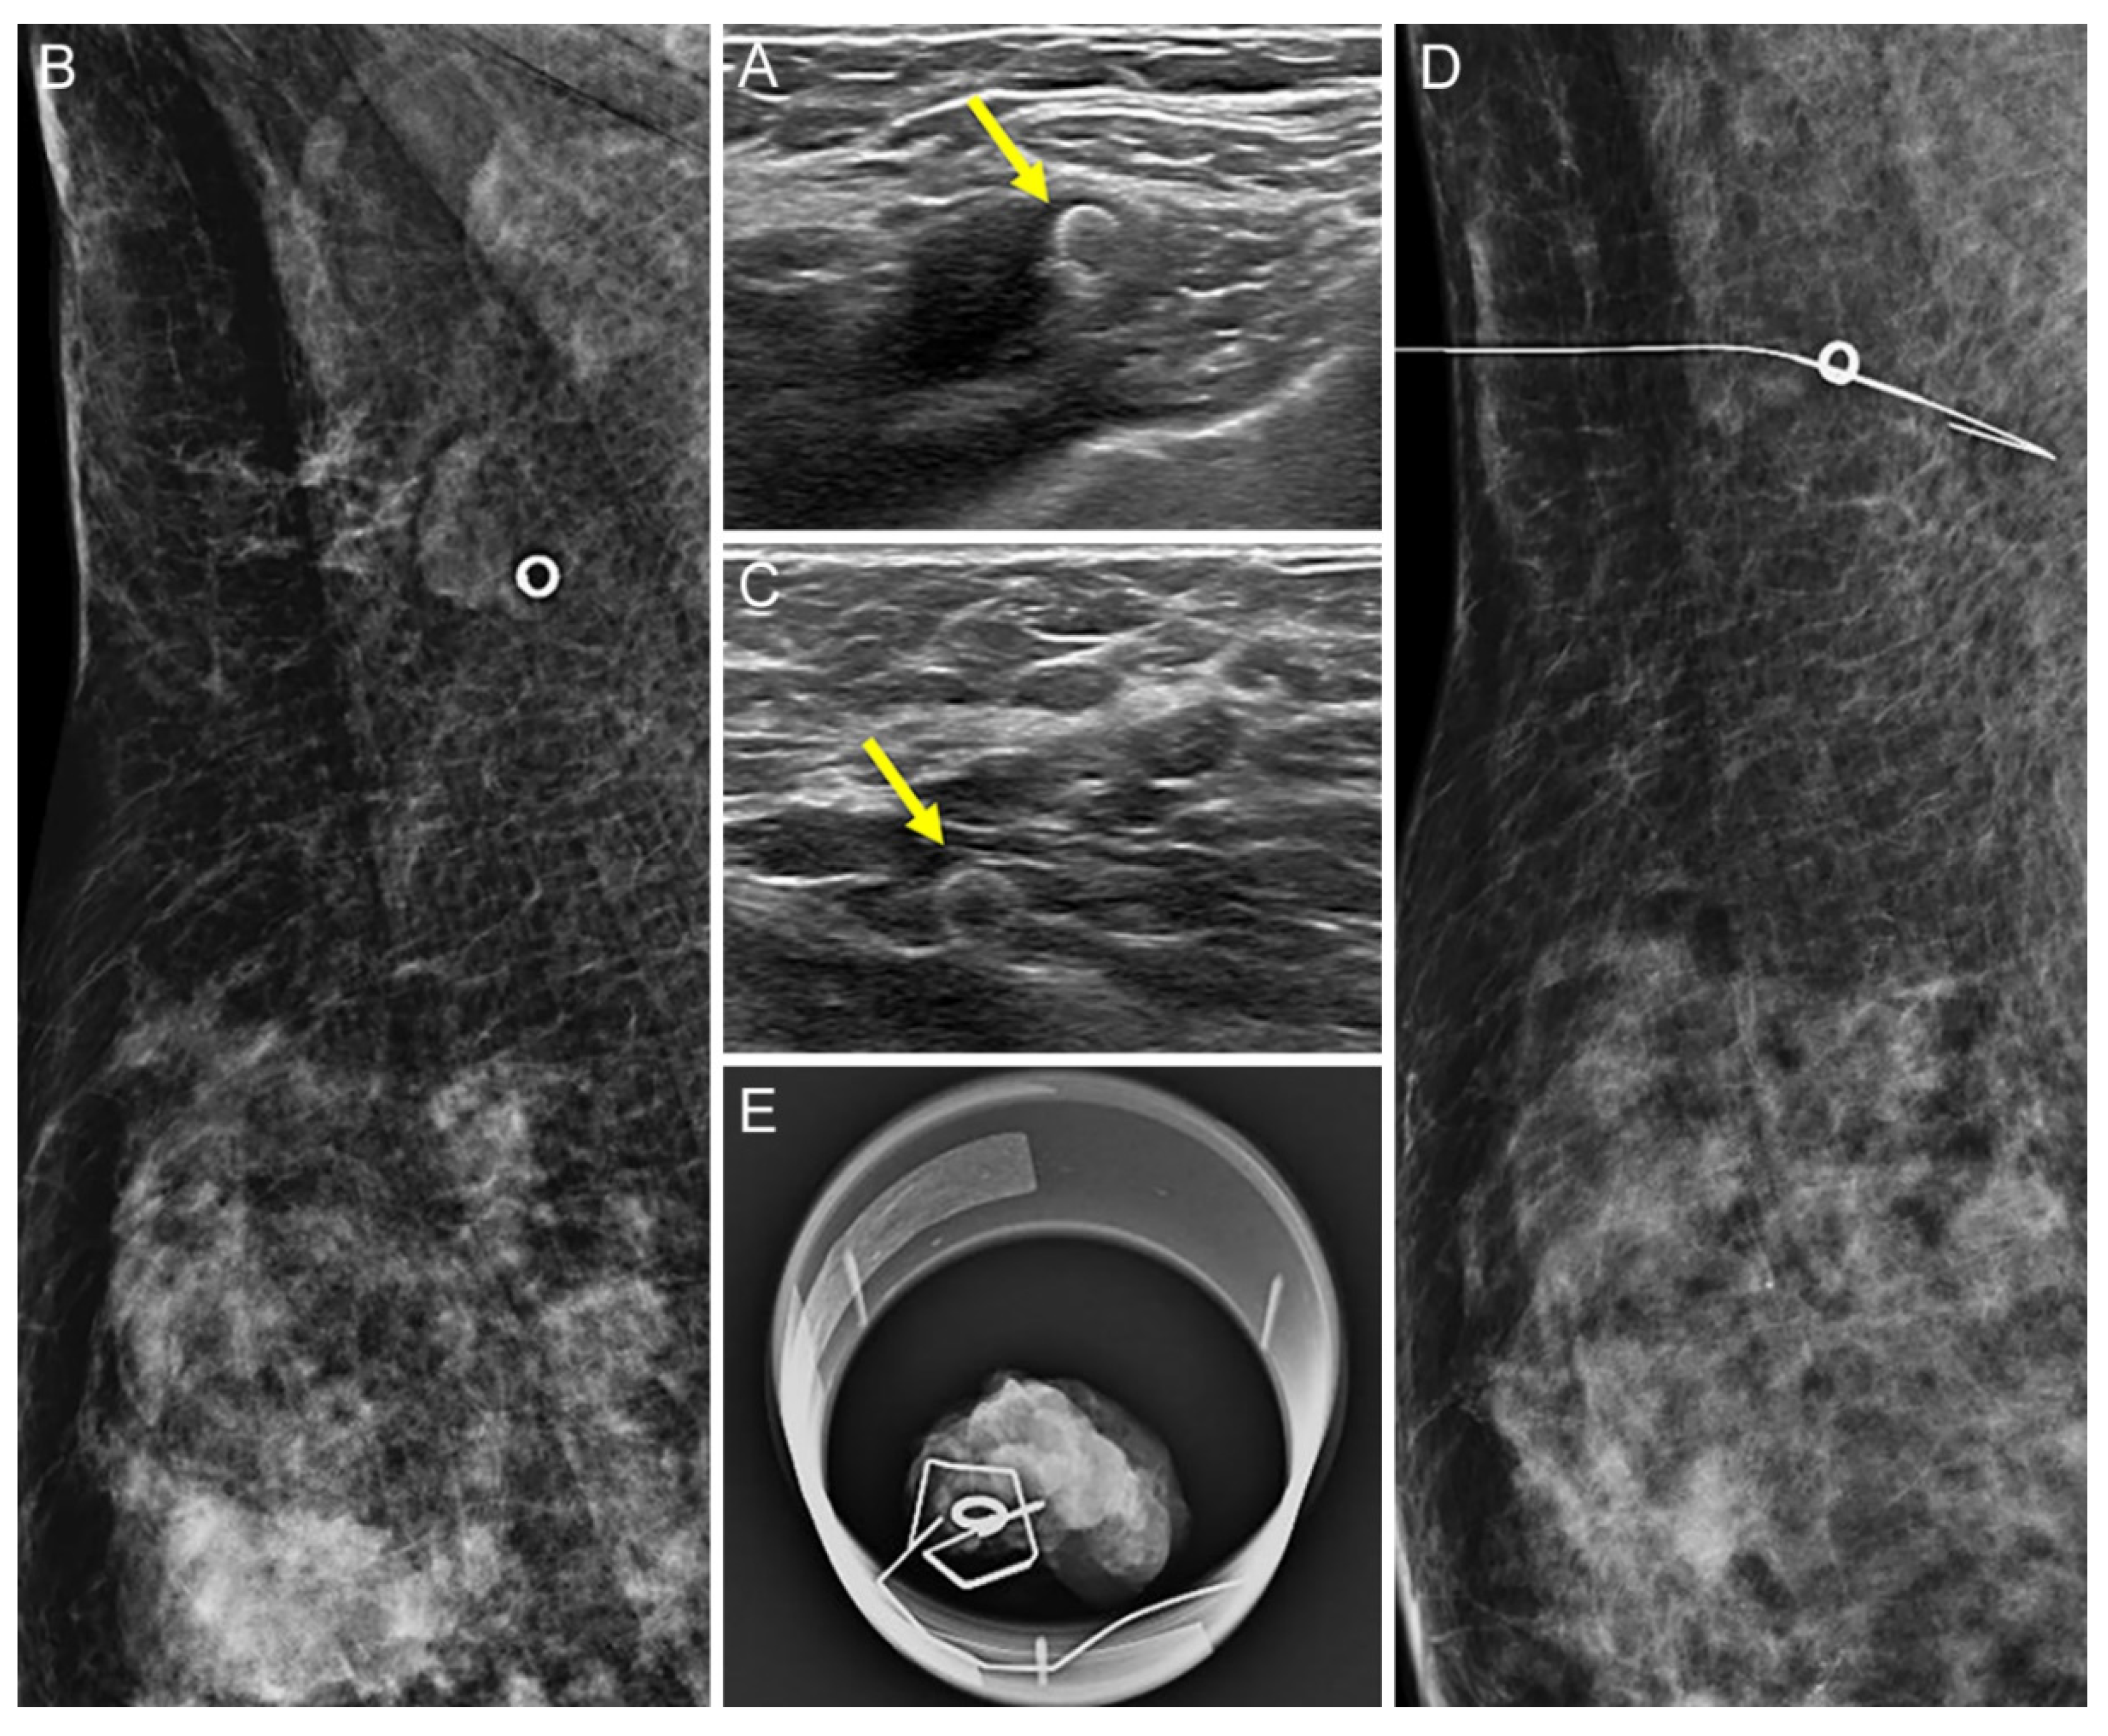

2.2. Tissue Marker Insertion for Axillary Lymph Nodes before NAC

2.3. Localization of Tissue Marker-Inserted Axillary Lymph Nodes after NAC

3.1. Comparison of the US Visibility between the Two Tissue Markers after NAC